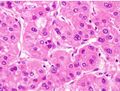

Pathology

Macroscopically, liver cancer appears as a nodular or infiltrative tumor. The nodular type may be solitary (large mass) or multiple (when developed as a complication of cirrhosis). Tumor nodules are round to oval, gray or green (if the tumor produces bile), well circumscribed but not encapsulated. The diffuse type is poorly circumscribed and infiltrates the portal veins, or the hepatic veins (rarely).[16]

Microscopically, the four architectural and cytological types (patterns) of hepatocellular carcinoma are: fibrolamellar, pseudoglandular (adenoid), pleomorphic (giant cell), and clear cell. In well-differentiated forms, tumor cells resemble hepatocytes, form trabeculae, cords, and nests, and may contain bile pigment in the cytoplasm. In poorly differentiated forms, malignant epithelial cells are discohesive, pleomorphic, anaplastic, and giant. The tumor has a scant stroma and central necrosis because of the poor vascularization.[39] A fifth form – lymphoepithelioma like hepatocellular carcinoma – has also been described.[40][41]